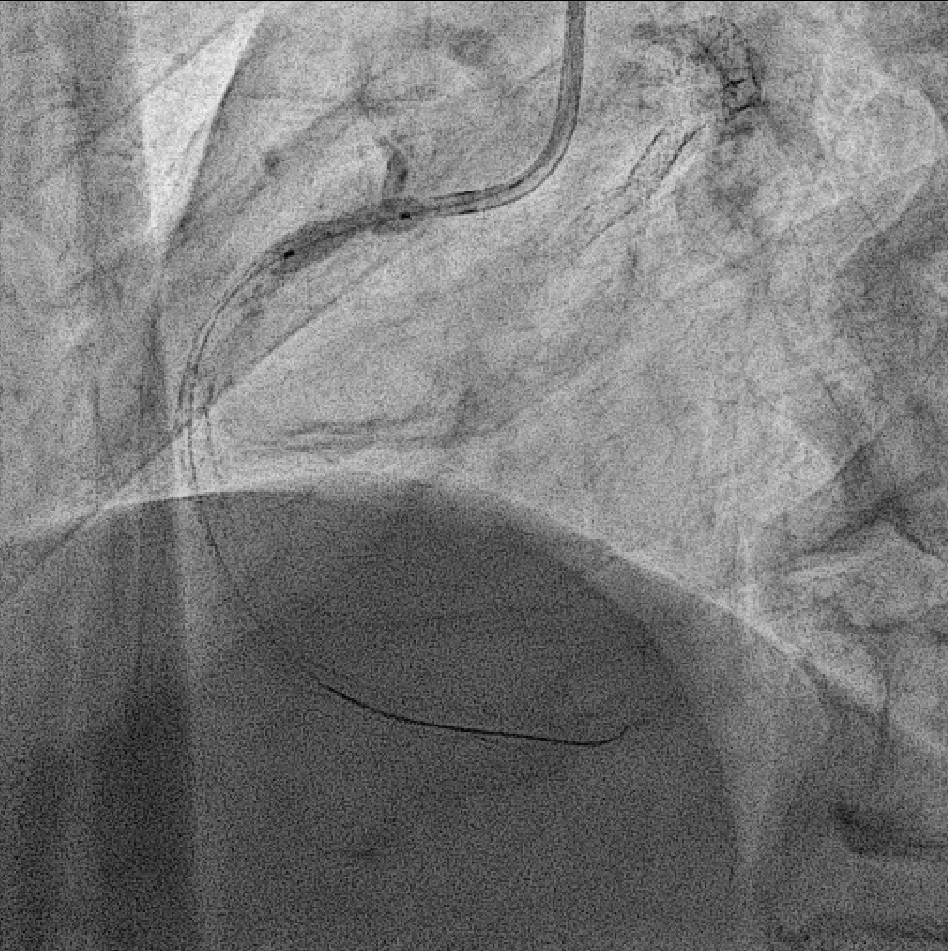

We advanced a 6F JR 4.0 SH 100cm guiding catheter and crossed the RCA ostial lesion using a Fielder FC guidewire. Pre-dilatation was performed with Ryurei 1.5¡¿15mm balloon. IVUS was then performed, revealing a patent stent in the proximal to mid RCA. However, the ostial RCA stent was under-expanded, with smooth muscle compressing the stent from outside. Balloon pre-dilatation was carried out using an NC Euphora 4.0¡¿12mm balloon, inflated up to 22 bar. However, the lesion was resistant and could not be fully dilated. We then applied a 4.0mm intravascular lithotripsy balloon with a total of 100 shocks delivered. But the effect was still minimal. The IVUS showed limited additional plaque fracture or vessel expansion. We tried NC Sapphire II 4.5¡¿8 mm balloon inflation to 18 bar, but it was ineffective due to balloon slippage. The angiogram after oversized NC dilation showed residual stenosis of 59%. We then selected a Wolverine Cutting Balloon 4.0¡¿10 mm and initiated dilation to 6 bar, which resulted in easy slippage again. Subsequent oversized dilations were performed at 18 bar, after which the lesion was successfully dilated. Using a Runthrough Floppy guidewire with the floating wire technique, a drug-eluting stent Biofreedom Ultra 4.0¡¿14 mm was deployed in the ostial RCA ISR. We inflated at 14 bar for 14 seconds, repeated twice. Final post-dilatation was performed with an Accuforce 4.0¡¿15mm balloon. The final IVUS showed good stent placement and expansion. We closed the procedure.